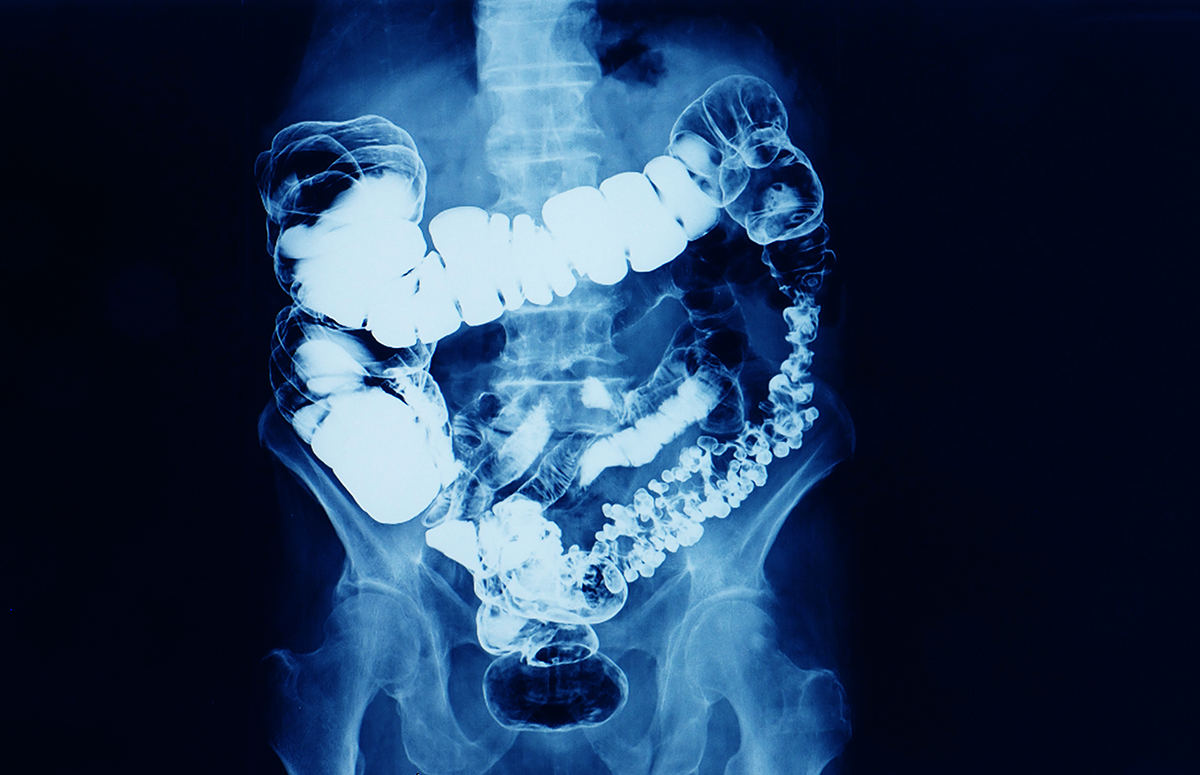

barium enema x-ray showing contrast fill in most part of large intestine such as transverse colon, sigmoid colon and rectum. the patient has colon cancer. medical film on dark background

健康な腸をつくるための食事ルール